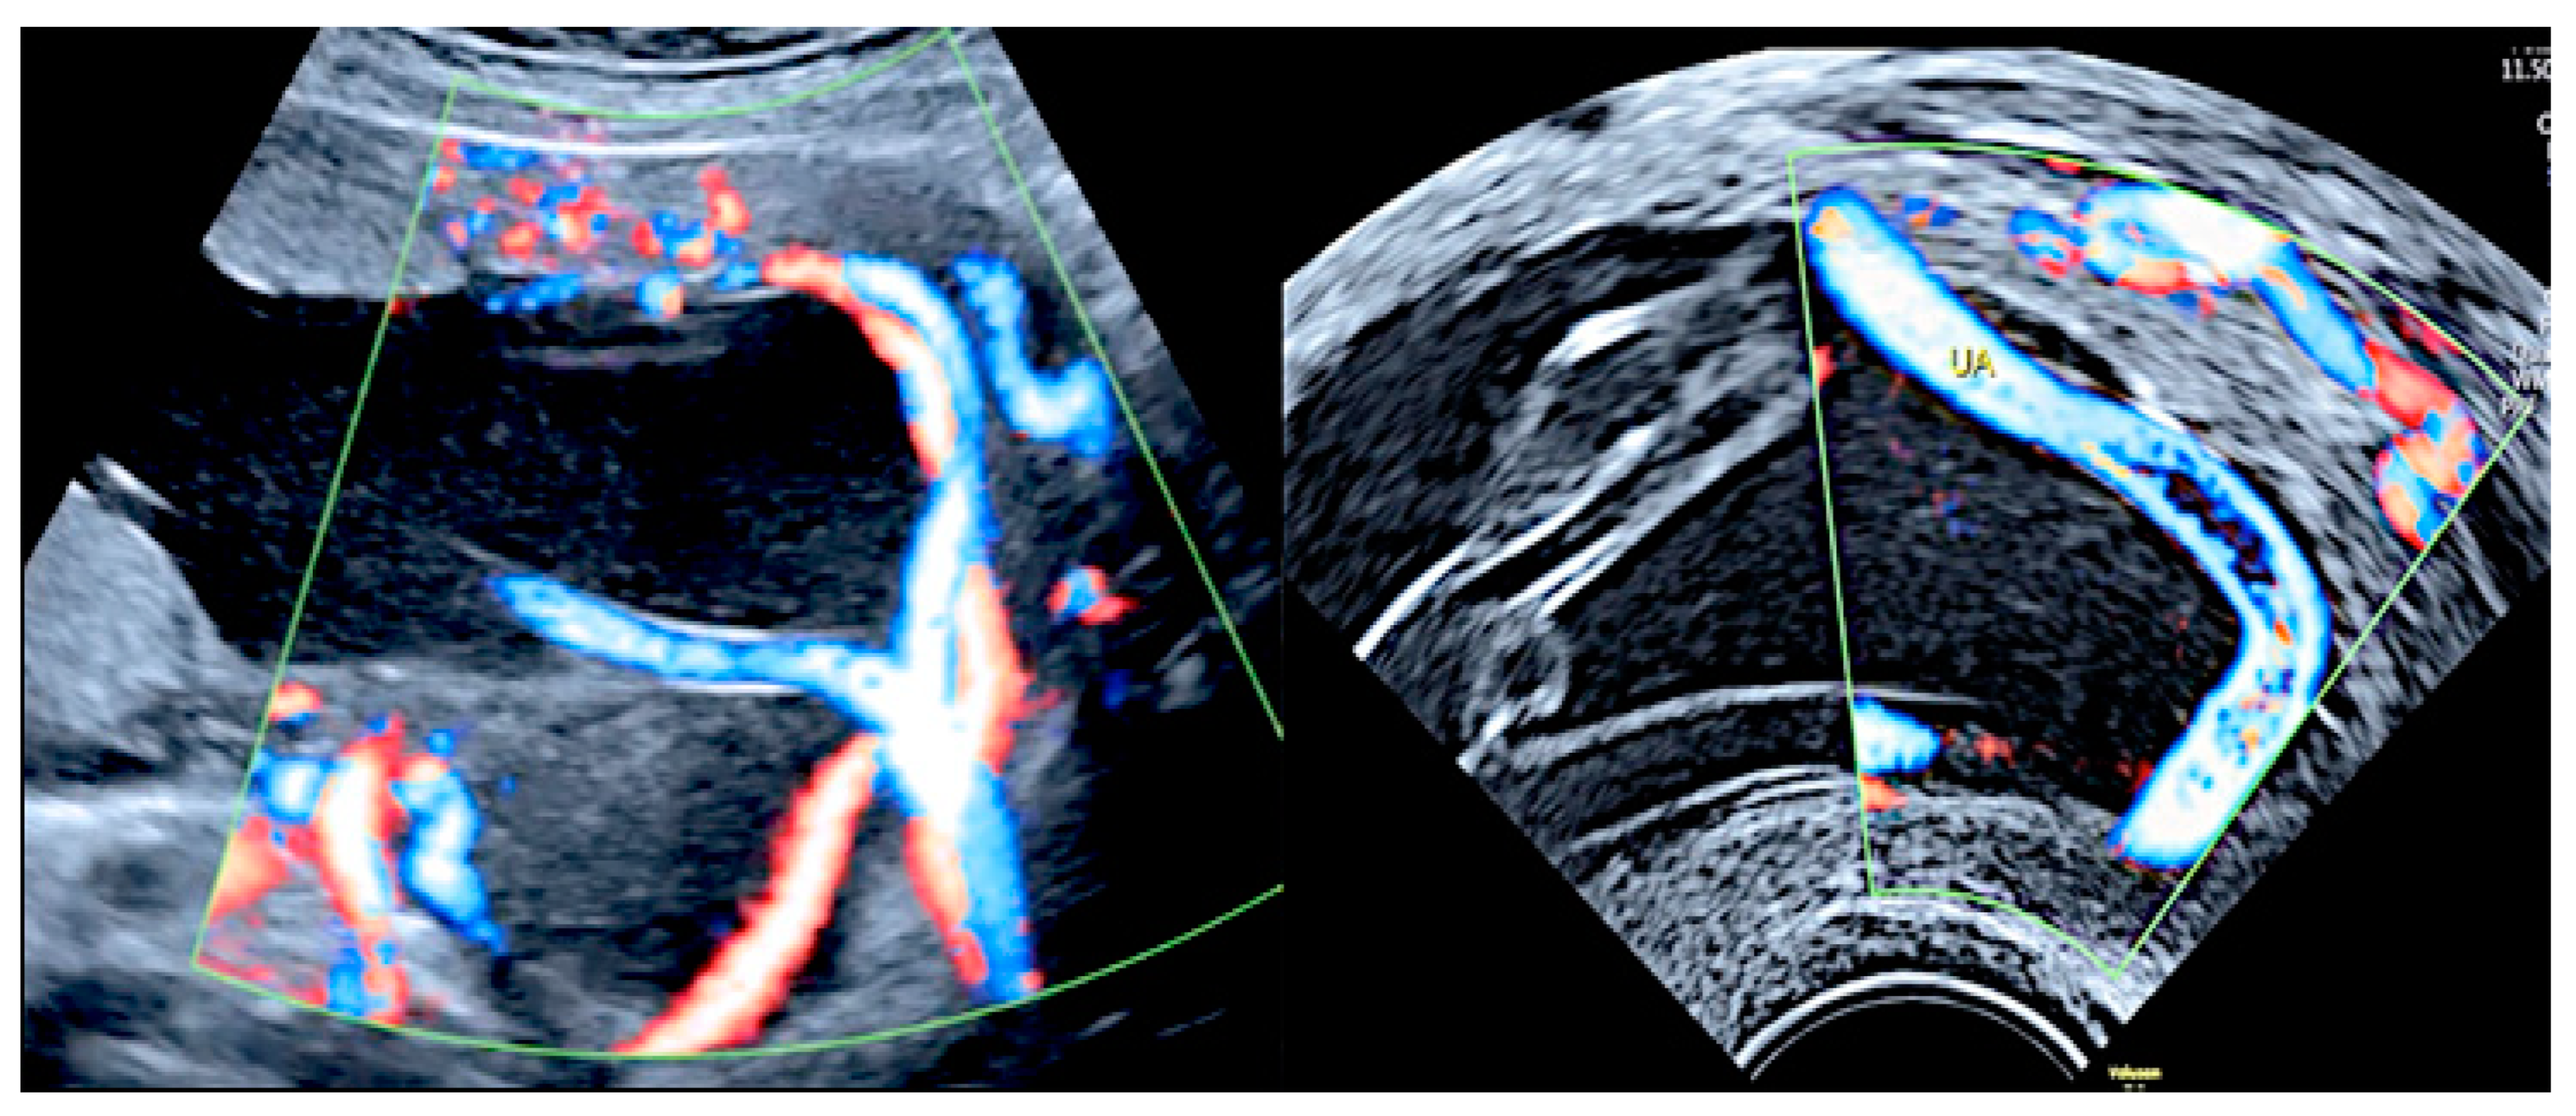

3.2.2. Vasa Praevia

3.2.3. Velamentous Umbilical Cord Insertion